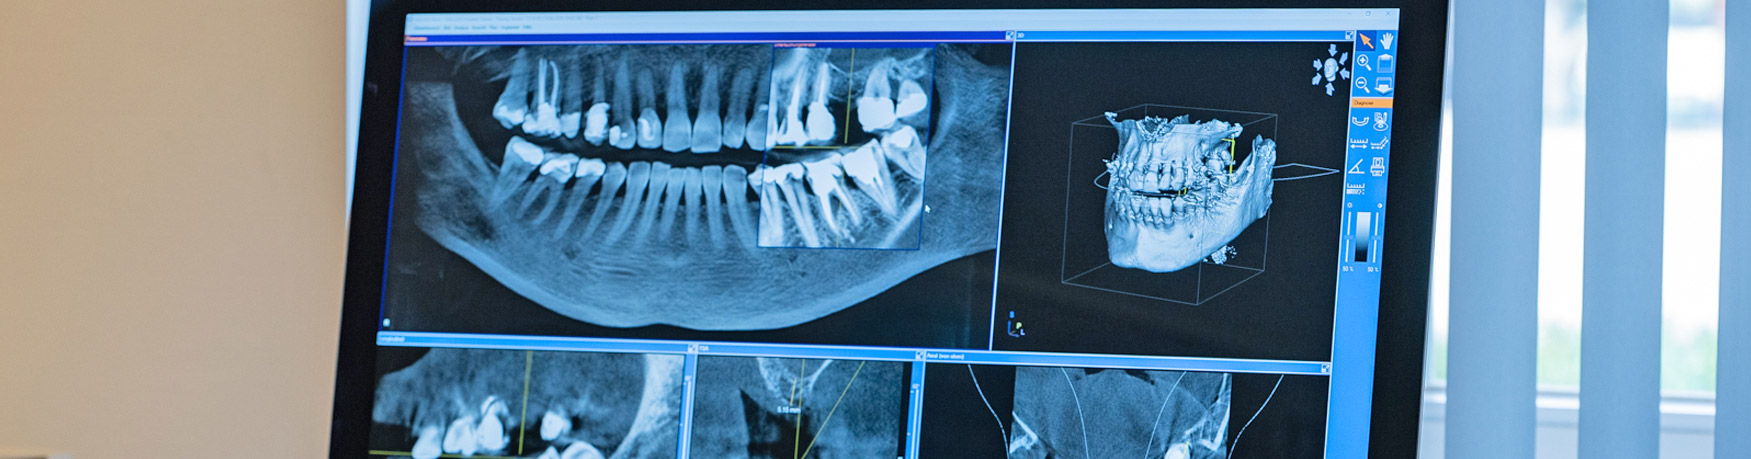

Digitale Volumen­tomographie (DVT)

Bei dem Digitalen Volumentomographen (DVT) handelt es sich um ein Hightech-Röntgengerät, das speziell für den Kopfbereich entwickelt wurde. Mit ihm können dreidimensionale Aufnahmen erstellt werden. Der wesentliche Vorteil von DVT-Aufnahmen ist, dass sie eine deutlich präzisere und aussagekräftigere Diagnostik ermöglichen:

Oft ist es zum Beispiel erst durch die 3D-Darstellung möglich, die exakte Breite des Kieferknochens zu erkennen oder den räumlichen Verlauf einer wichtigen Nervenbahn zu beurteilen und diese entsprechend zu schützen.

1. Die DVT liefert einzelne Querschnittsbilder des Kiefers bzw. des gesamten Kopfes.

2. Diese Einzelaufnahmen können entweder direkt zur maßstabsgetreuen Vermessung verwendet oder mit Hilfe eines Computerprogramms zu einem Komplettbild des Kiefers zusammengefügt werden.

3. Das Komplettbild steht dann am Monitor beispielsweise für die computerunterstützte 3D-Implantatplanung zur Verfügung.